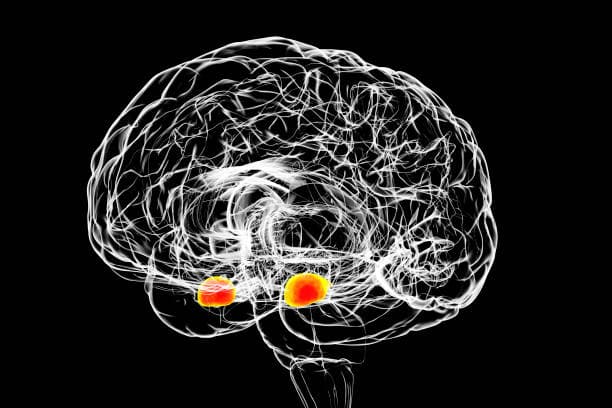

Already after a single Mind Switch® Fear & Phobia App application of 100 minutes, there was a significant reduction in four brain areas, including the amygdala (main fear center in the brain), by an average of 79%.

"After repeated use (Total 5 hours per personon average, spread over 4 weeks) of the Mind Switch® Fear & Phobia App, a strong reduction in the response to images of spiders was demonstrated in brain areas usually strongly associated with phobias: In the right amygdala, average activity was reduced by 117%, and in the left amygdala by an average of 145%. In the visual areas of the brain, there was a reduction from 8 units to an average of -1.6 units, in somatosensory-motor regions from 15.1 to - 2.8 units, in the parietal lobe from 8.6 to -5.3 units, and in the cerebellum from an average of 12.2 to 2.7 units. In summary, these results clearly indicate that in people suffering from phobias, a significant reduction in brain activity is observed with repeated use of the app. And this is in brain areas associated with anxiety."

Amygdala